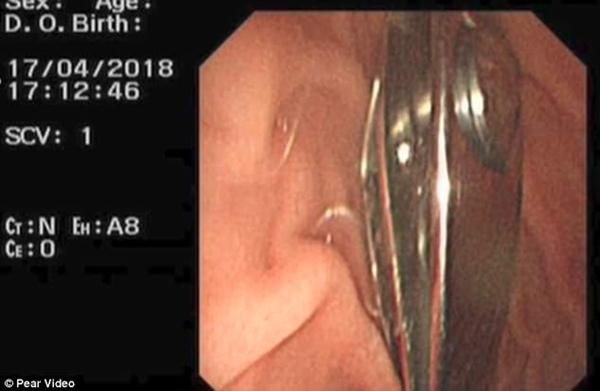

Sau khi chụp X-quang, bác sĩ phát hiện ra chiếc bấm móng tay dài 2,4 inch (khoảng 6cm) đã nằm gọn trong dạ dày của Phi Phi. Các bác sĩ phải thực hiện phẫu thuật gây tê tổng quát, nội soi mất 25 phút đồng hồ để lấy cho được dị vật ra khỏi khoang bụng cậu bé.

Hình ảnh X-quang cho thấy chiếc bấm móng tay nằm trong dạ dày của Phi Phi.